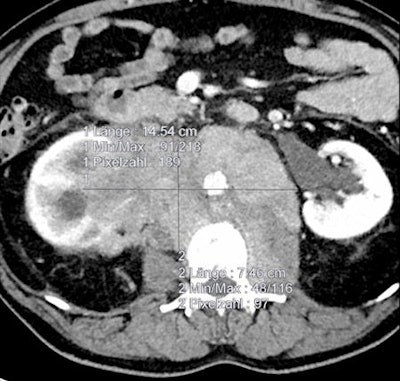

As shown in these cases, volumetry is more sensitive than RECIST measurements for determining therapy treatment response. All images courtesy of Dr. Anno Graser.

In patient data from the CRYSTAL metastatic colorectal treatment trial, RECIST measurements showed early tumor shrinkage of 15.4%. But volumetry revealed early tumor shrinkage of 61.5%, Graser said.